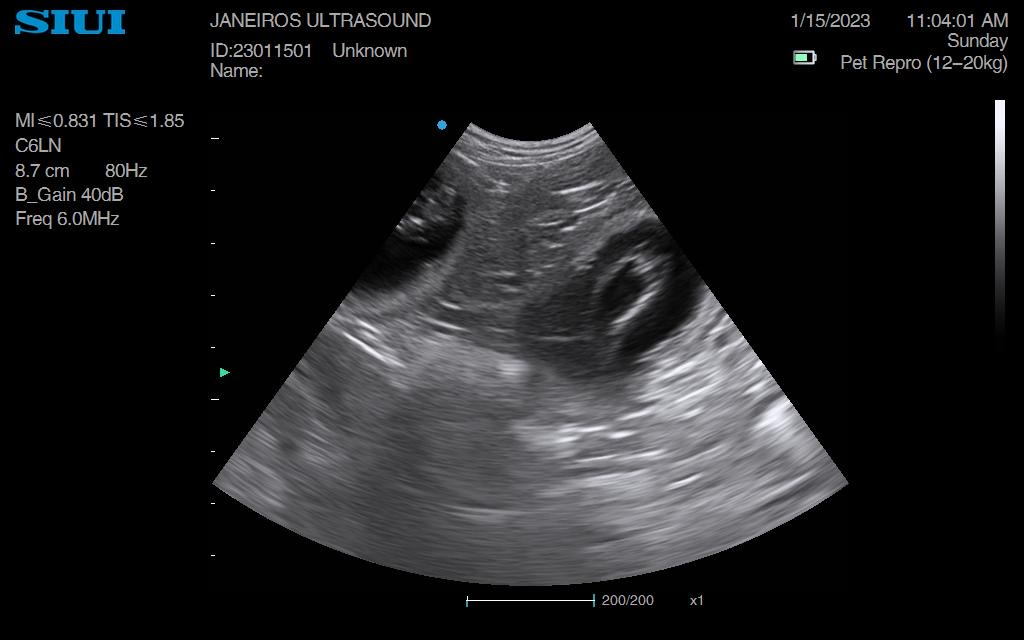

Nel, Dachshund Pregnancy Scan Conisbrough

Had the pleasure of meeting and scanning this girl. Pregnancy confirmed and we saw 6 gestational sacs. Excited to see these beauties born, sire is a very handsome black &